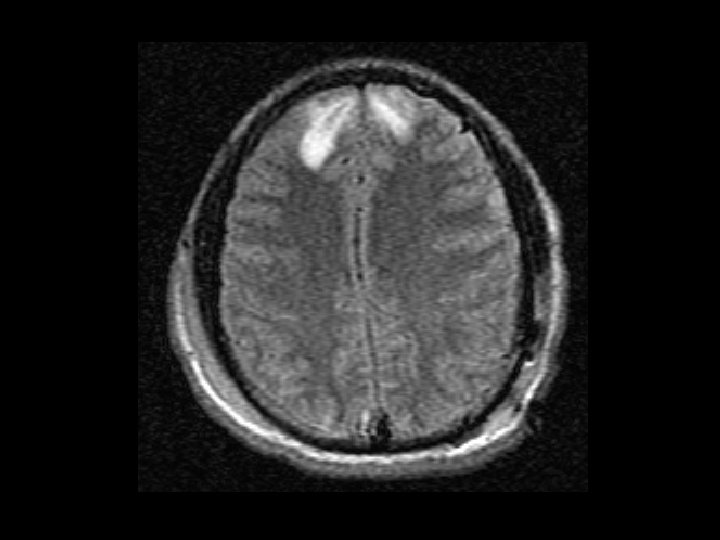

Diffuse Axonal Injury (DAI) • Shearing and rotational forces disrupt the axonal network • Mechanism: rapid acceleration/deceleration injury • Imaging – Not well visualized by CT – MRI can better define the extent of injury • No specific therapy • Likely results in the persistent neurologic deficits in patients with normal CT scans but substantial injury

Diagnostic Testing • MRI: – Better than CT – May show diffuse axonal injury and injuries not identified by CT scan – Not used as a routine screening test • 30 – 45 minutes to obtain images • Very costly and not always available